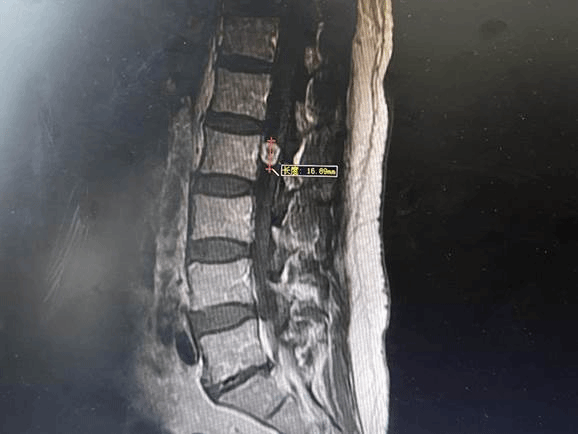

入院后,经过全面检查发现,肿瘤位于腰二锥体后方的椎管内,大小约1.6厘米。孙颖教授带领团队经过讨论决定为其进行显微镜下经脊柱微通道完整切除神经鞘瘤。